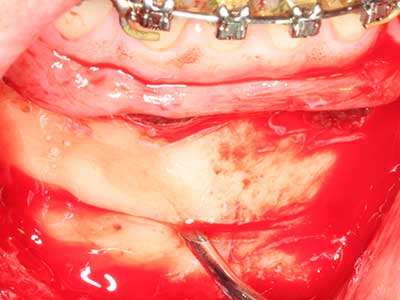

Fig. 7: La preparación inicial de la mucosa del seno maxilar también puede realizarse asistida por ultrasonidos.

Fig. 8: Una vez realizada la elevación del seno, la partición crestal del hueso se fija en la cresta maxilar deficitaria.

Fig. 9: Rebase con material de reemplazo óseo bovino (Cerabone 0,5-1mm, Botiss Bio-materials, Berlín) y hueso autógeno (vista palatinal).

Fig. 10: Cobertura del área aumentada con una membrana pericárdica estable a largo plazo (Jason Kollagenmembran, Botiss).

Fig. 11: El ortopantomograma posoperatorio presenta el aumento vertical y la elevación del suelo del seno.